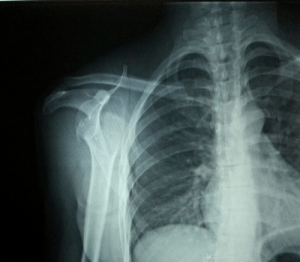

Si tratta di una donna di 42 anni, la quale a seguito di una caduta laterale sulla spalla destra ha riportato una lussazione posteriore della spalla destra (foto n° 1) e frattura parzialmente scomposta del trochite (foto n° 2).

Dopo 2 giorni e stato richiesta nuova Rx per studio completo della spalla dx al fine di visualizzare meglio la frattura in corso.

Al controllo radiologico dopo un mese viene rilevato un parziale consolidamento della frattura.

Da come si può notare dall’ultimo RX si rileva il perfetto allineamento del Trochite.